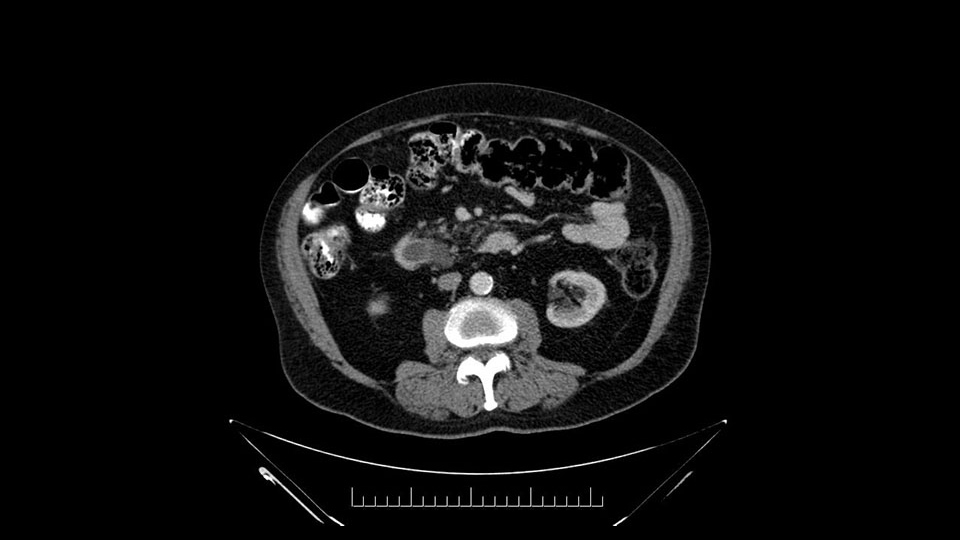

Then look at the first jejunal branch - which is this thing here - this little branch which goes under the SMA. It’s something that we’ve just started appreciating over the past few years and the reason for that is: there’s two or three small branches that come out of the uncinate into the the first jejunal and it’s a fairly inevitable part of the operation where there’s some bleeding. As long as you’re cognizant of what’s happening, it’s no reason to panic and that kind of bleeding will eventually stop or can be stopped but it’s not easy because these little vessels are fragile from the uncinate to the first jejunal. So I do focus on that and it’s pretty consistent I’d say 9 times out of 10, people have that first jejunal.

In planning for my further steps, the first key that I find, first do a gentle mobilization of the hepatic flexure of colon completely away because that’s going to help me do a good wide Kocher maneuver. Why do I slow down? Because there are small tributaries and small blood vessels which communicate between the transverse mesocolon and the head of the pancreas and you also have the loop of Henle all the blood vessels which drain into the superior mesenteric vein just as it gets underneath the neck of the pancreas.

Other important points are: the dissection of the uncinate process which must be done very carefully, the ligation of the venous branches there, and looking for the inferior pancreaticoduodenal arteries coming from the superior mesenteric artery during the dissection of the uncinate process.

Once the pancreatic neck is divided, you sort of roll or flip the neck of the gland over, exposing the anterior surface and the right lateral surface of the portal vein-SMV complex. Continue that dissection down. Oftentimes you can really continue your dissection right along the uncinate on the SMA. Again a little advantage of this patient having an ampullary lesion, there's likely to be no evidence of extension into the uncinate so you don't have to worry quite as much about the margin at the uncinate as you would with a pancreatic head cancer. Keeping in mind that you will have an inferior pancreatic duodenal artery in there that you want to try to identify and ligate individually. At some point along that time I go to the ligament of Treitz. Clean an area of the ligament of Treitz of its mesentery, divide it there with a linear stapler. I use the Harmonic scalpel to mobilize the proximal 10-inches or so of small intestine down to the ligament of Treitz completely mobilize the ligament of Treitz past the jejunal limb underneath the root of the mesentery and then carefully dissect the third and fourth portion of the duodenum’s mesentery as well as the remaining uncinate to complete my resection. I will have marked and sent frozen section from the pancreatic neck at the time that I do the resection of that part of the gland so that I have that information back by now. I would also probably get a margin on the uncinate and a margin on the bile duct just for completeness, although for an ampullary carcinoma that would be unlikely to have a positive extension.